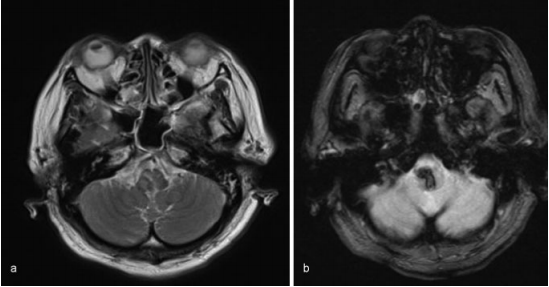

入院后,她出现白天呼吸控制(每分钟呼吸10次)和夜间呼吸暂停。然后她被插管,并用呼吸机控制呼吸。MRI未发现明显的出血原因,如海绵状畸形、动静脉畸形或肿瘤。患者随后被诊断为高血压原发性延髓出血,随后通过持续静脉注射钙通道阻滞剂来降低血压。然而,病人的呼吸控制没有好转。

图:磁共振图像显示出血没有明显的病理原因,(a)T2加权(b)T2加权。